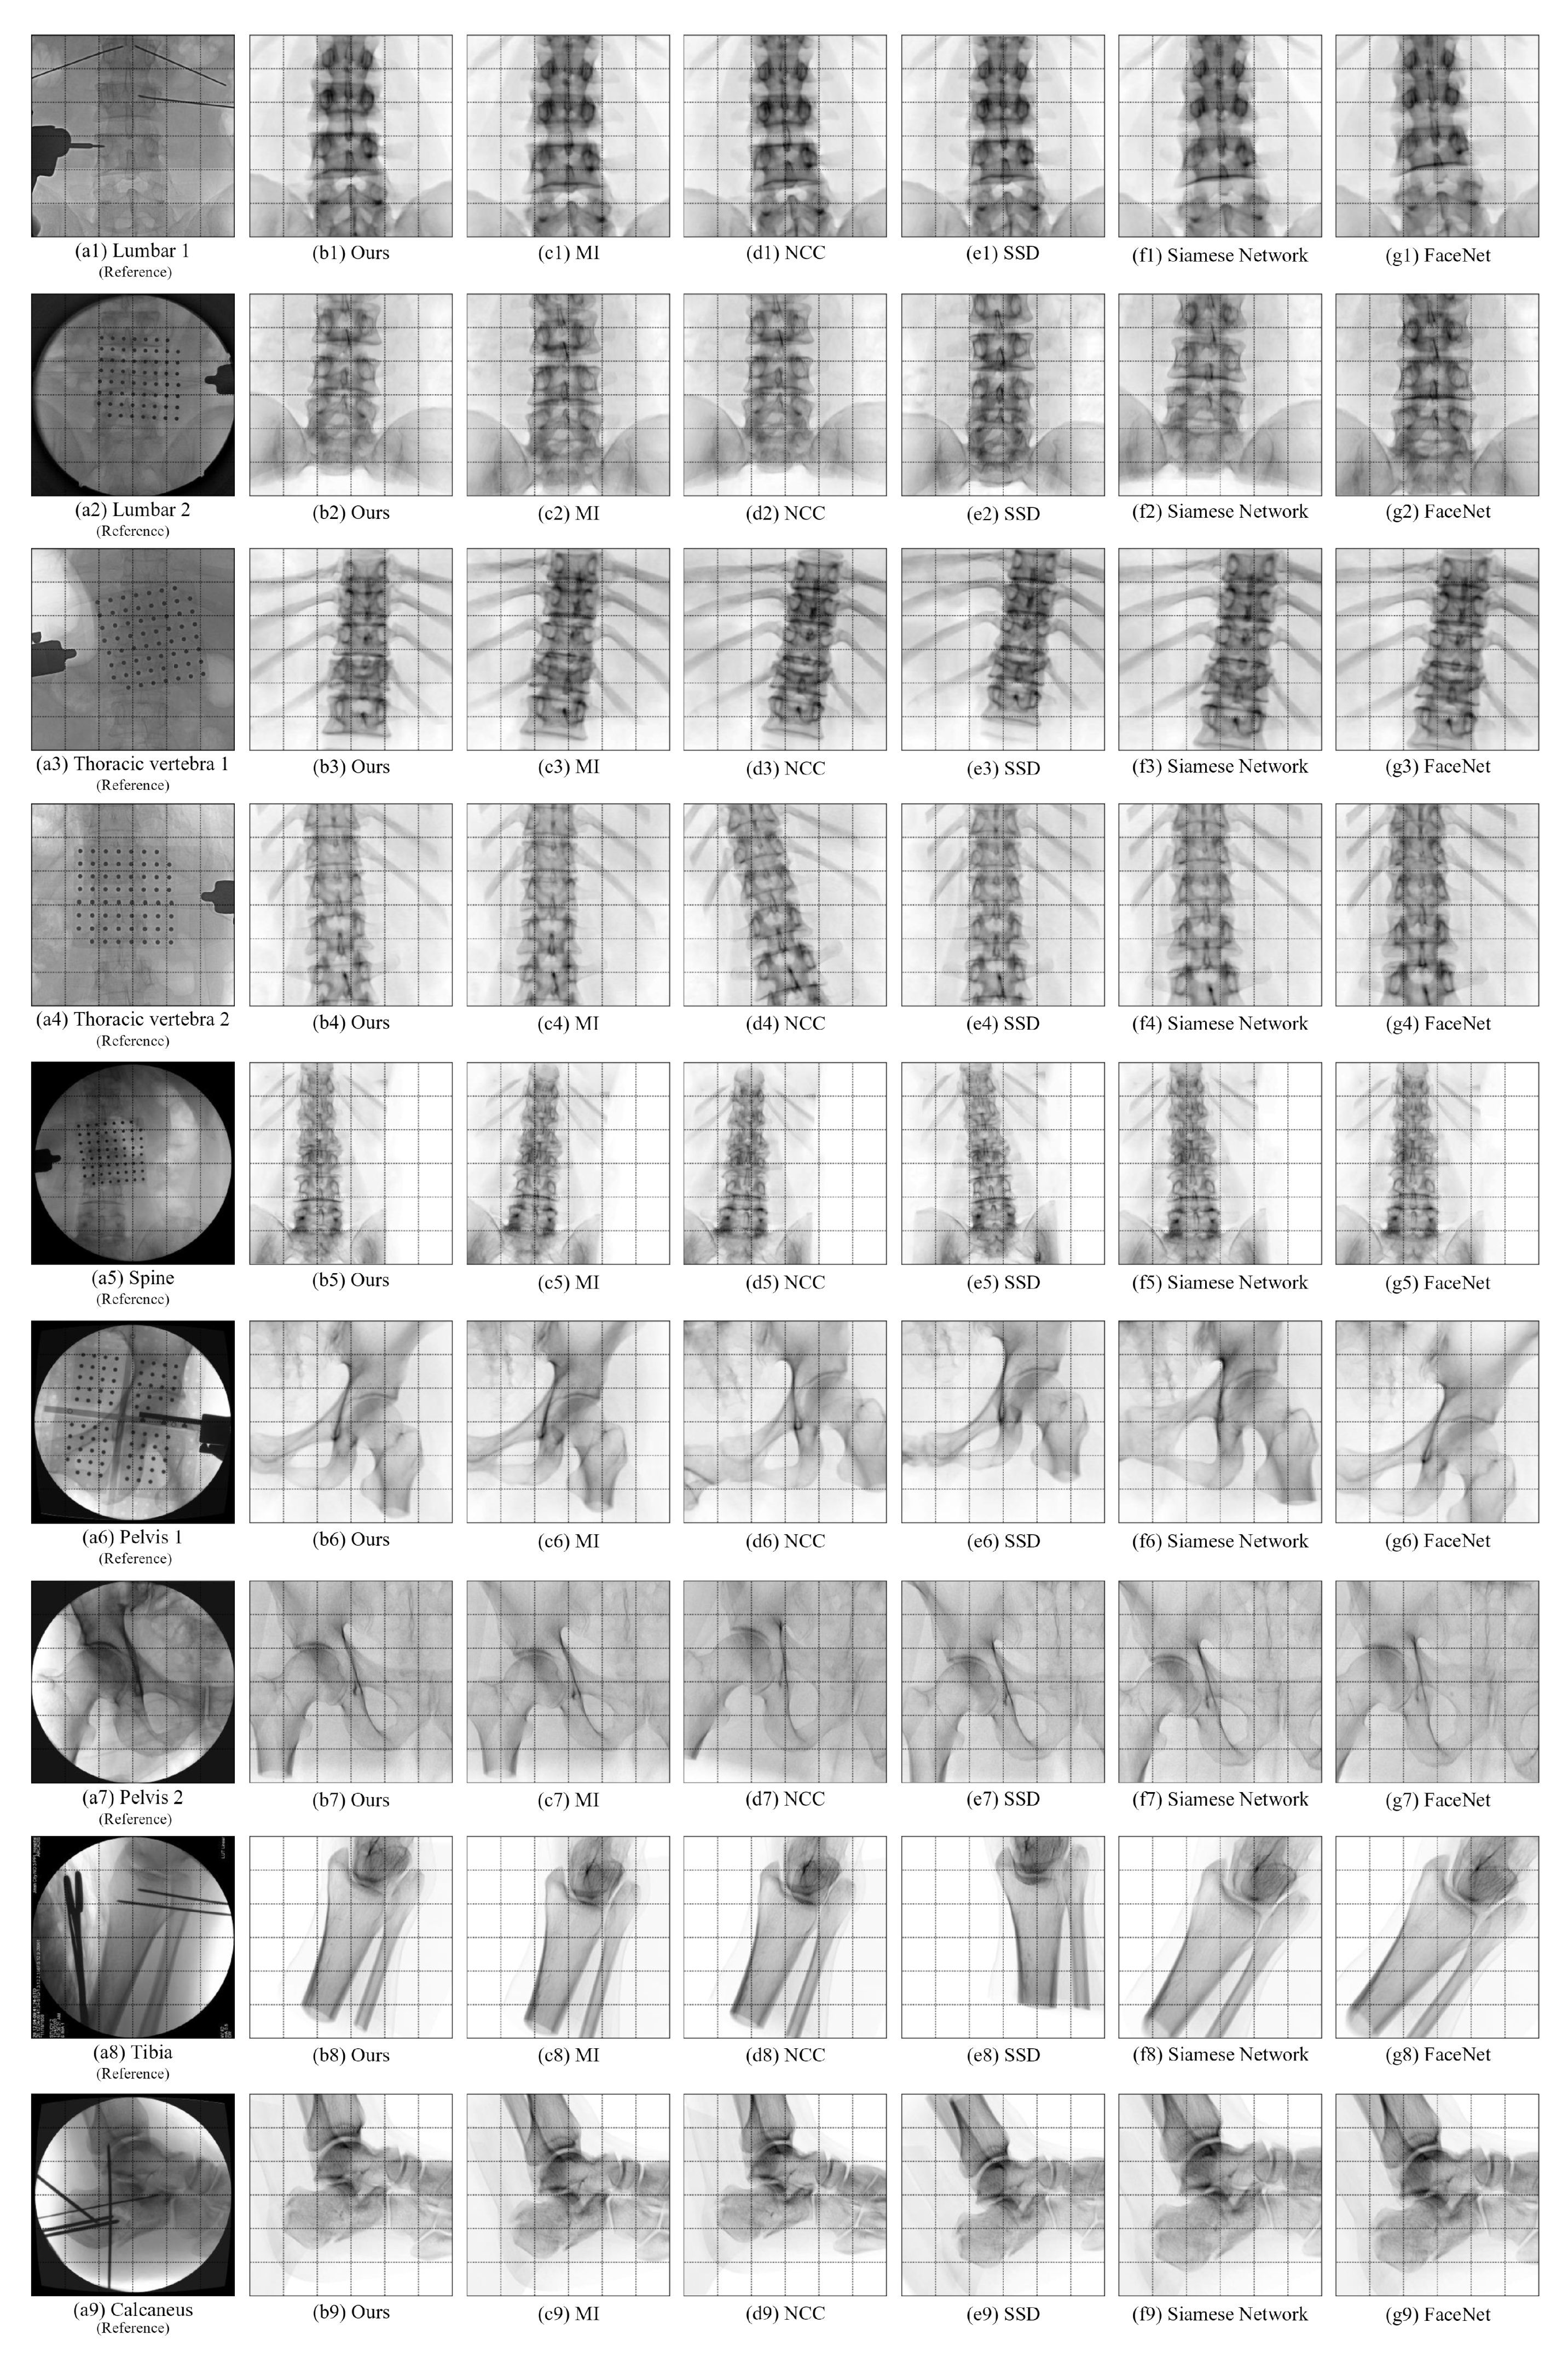

4.5. Comparative Experiments of Registration Algorithms

| Algorithm | Bone Type | Average Error of X Rotation / ° | Average Error of Y Rotation / ° | Average Error of Z Rotation / ° | Average Error of X Translation / mm | Average Error of Y Translation / mm | Average Error of Z Translation / mm | Average Registration Time / s |

|---|---|---|---|---|---|---|---|---|

| SSD | Lumbar 1 | 3.723 | 4.578 | 3.986 | 3.052 | 5.005 | 8.690 | 61.08 |

| Lumbar 2 | 3.690 | 2.468 | 2.726 | 2.267 | 16.194 | 8.639 | ||

| Lumbar 3 | 2.598 | 5.953 | 1.463 | 1.581 | 5.183 | 10.356 | ||

| Thoracic vertebra 1 | 13.035 | 8.614 | 3.915 | 8.009 | 1.223 | 8.464 | ||

| Thoracic vertebra 2 | 5.951 | 1.160 | 1.792 | 4.799 | 1.286 | 10.555 | ||

| Thoracic vertebra 3 | 5.142 | 1.712 | 3.950 | 5.484 | 8.544 | 15.533 | ||

| Thoracic vertebra 4 | 4.620 | 4.316 | 2.114 | 16.006 | 1.751 | 14.582 | ||

| Spine | 10.234 | 1.740 | 1.617 | 12.165 | 3.361 | 11.208 | ||

| Pelvis 1 | 11.077 | 5.547 | 2.511 | 3.837 | 2.663 | 6.221 | ||

| Pelvis 2 | 4.744 | 2.534 | 1.651 | 2.875 | 3.402 | 14.787 | ||

| Tibia | 4.550 | 9.989 | 9.410 | 10.999 | 4.369 | 5.166 | ||

| Calcaneus | 2.750 | 4.440 | 12.936 | 1.675 | 7.716 | 13.753 | ||

| NCC | Lumbar 1 | 3.258 | 1.683 | 0.737 | 2.212 | 7.603 | 4.182 | 61.80 |

| Lumbar 2 | 1.267 | 1.759 | 1.422 | 1.091 | 2.098 | 4.027 | ||

| Lumbar 3 | 3.898 | 1.172 | 0.560 | 2.163 | 7.645 | 5.649 | ||

| Thoracic vertebra 1 | 9.279 | 4.383 | 0.833 | 7.519 | 5.109 | 6.742 | ||

| Thoracic vertebra 2 | 6.402 | 4.854 | 4.558 | 2.816 | 6.941 | 4.325 | ||

| Thoracic vertebra 3 | 4.497 | 1.401 | 3.986 | 5.094 | 7.301 | 9.764 | ||

| Thoracic vertebra 4 | 9.643 | 1.157 | 1.281 | 9.412 | 0.184 | 7.363 | ||

| Spine | 7.598 | 0.115 | 1.024 | 8.685 | 9.761 | 11.525 | ||

| Pelvis 1 | 3.774 | 9.057 | 8.350 | 9.205 | 11.867 | 3.560 | ||

| Pelvis 2 | 8.481 | 4.837 | 6.500 | 8.868 | 3.868 | 4.276 | ||

| Tibia | 9.374 | 8.001 | 7.040 | 2.810 | 5.012 | 5.138 | ||

| Calcaneus | 0.207 | 6.988 | 2.897 | 2.899 | 1.881 | 15.986 | ||

| MI | Lumbar 1 | 5.976 | 2.148 | 2.408 | 1.310 | 7.922 | 5.484 | 59.41 |

| Lumbar 2 | 7.576 | 1.030 | 0.467 | 0.854 | 9.813 | 3.748 | ||

| Lumbar 3 | 4.917 | 4.354 | 0.276 | 3.746 | 6.800 | 3.947 | ||

| Thoracic vertebra 1 | 6.506 | 2.365 | 1.077 | 8.694 | 1.595 | 3.794 | ||

| Thoracic vertebra 2 | 1.422 | 0.936 | 3.358 | 3.156 | 2.775 | 6.203 | ||

| Thoracic vertebra 3 | 7.899 | 3.544 | 1.844 | 0.714 | 4.794 | 8.123 | ||

| Thoracic vertebra 4 | 6.546 | 2.873 | 6.148 | 0.469 | 2.295 | 5.637 | ||

| Spine | 5.510 | 0.364 | 3.185 | 8.540 | 4.761 | 2.559 | ||

| Pelvis 1 | 2.762 | 1.364 | 1.973 | 9.802 | 0.840 | 5.788 | ||

| Pelvis 2 | 3.879 | 3.054 | 1.795 | 5.028 | 1.882 | 7.962 | ||

| Tibia | 7.399 | 6.420 | 3.047 | 1.071 | 8.159 | 5.883 | ||

| Calcaneus | 5.769 | 6.759 | 4.747 | 1.359 | 4.488 | 7.308 | ||

| Siamese Network [17] | Lumbar 1 | 12.321 | 1.156 | 2.452 | 2.390 | 4.013 | 9.817 | 85.90 |

| Lumbar 2 | 10.792 | 3.091 | 0.907 | 3.632 | 6.290 | 8.256 | ||

| Lumbar 3 | 5.071 | 1.233 | 1.721 | 7.114 | 5.561 | 9.095 | ||

| Thoracic vertebra 1 | 4.698 | 4.640 | 1.096 | 6.680 | 3.713 | 14.319 | ||

| Thoracic vertebra 2 | 8.912 | 4.417 | 2.791 | 1.086 | 2.338 | 11.113 | ||

| Thoracic vertebra 3 | 2.169 | 1.273 | 3.541 | 1.478 | 6.854 | 12.723 | ||

| Thoracic vertebra 4 | 7.006 | 2.799 | 1.371 | 4.092 | 2.346 | 13.122 | ||

| Spine | 6.778 | 3.513 | 1.049 | 6.110 | 4.078 | 7.576 | ||

| Pelvis 1 | 10.407 | 3.111 | 5.189 | 4.311 | 5.125 | 6.297 | ||

| Pelvis 2 | 4.598 | 2.691 | 1.745 | 8.870 | 6.588 | 5.394 | ||

| Tibia | 7.967 | 9.225 | 3.046 | 0.104 | 10.223 | 11.749 | ||

| Calcaneus | 3.519 | 6.179 | 9.991 | 2.709 | 2.361 | 13.900 | ||

| FaceNet [19] | Lumbar 1 | 10.492 | 1.529 | 2.118 | 1.048 | 2.653 | 6.935 | 83.97 |

| Lumbar 2 | 12.086 | 2.478 | 1.754 | 1.487 | 8.517 | 14.821 | ||

| Lumbar 3 | 11.723 | 5.121 | 1.790 | 5.137 | 6.051 | 8.622 | ||

| Thoracic vertebra 1 | 6.208 | 2.650 | 1.207 | 3.987 | 7.017 | 11.059 | ||

| Thoracic vertebra 2 | 13.220 | 3.072 | 1.253 | 2.421 | 1.769 | 10.890 | ||

| Thoracic vertebra 3 | 9.350 | 2.131 | 6.797 | 0.339 | 10.311 | 12.198 | ||

| Thoracic vertebra 4 | 8.563 | 4.131 | 3.147 | 8.157 | 3.768 | 8.893 | ||

| Spine | 9.116 | 2.266 | 1.576 | 10.652 | 7.985 | 7.920 | ||

| Pelvis 1 | 4.897 | 3.762 | 8.898 | 9.023 | 9.158 | 9.114 | ||

| Pelvis 2 | 9.766 | 2.048 | 4.638 | 8.412 | 3.551 | 4.645 | ||

| Tibia | 4.457 | 6.847 | 11.349 | 1.032 | 8.848 | 15.491 | ||

| Calcaneus | 1.551 | 5.217 | 9.441 | 2.222 | 5.412 | 10.160 | ||

| Ours | Lumbar 1 | 0.916 | 0.465 | 0.304 | 0.182 | 0.248 | 1.400 | 61.38 |

| Lumbar 2 | 0.750 | 0.353 | 1.812 | 0.132 | 0.712 | 0.438 | ||

| Lumbar 3 | 0.492 | 1.171 | 0.657 | 0.065 | 0.670 | 0.577 | ||

| Thoracic vertebra 1 | 0.120 | 0.336 | 0.240 | 0.677 | 0.223 | 0.489 | ||

| Thoracic vertebra 2 | 0.212 | 0.555 | 0.834 | 0.348 | 0.639 | 0.375 | ||

| Thoracic vertebra 3 | 0.912 | 0.884 | 0.796 | 1.003 | 0.664 | 0.633 | ||

| Thoracic vertebra 4 | 0.986 | 0.425 | 0.765 | 1.036 | 1.674 | 0.401 | ||

| Spine | 0.727 | 0.271 | 0.414 | 0.277 | 0.730 | 0.837 | ||

| Pelvis 1 | 0.614 | 0.545 | 0.143 | 0.674 | 0.723 | 0.520 | ||

| Pelvis 2 | 0.914 | 0.832 | 0.416 | 0.266 | 0.215 | 0.297 | ||

| Tibia | 0.628 | 0.956 | 0.883 | 0.355 | 0.359 | 0.496 | ||

| Calcaneus | 0.294 | 0.158 | 0.904 | 0.331 | 0.753 | 0.217 |